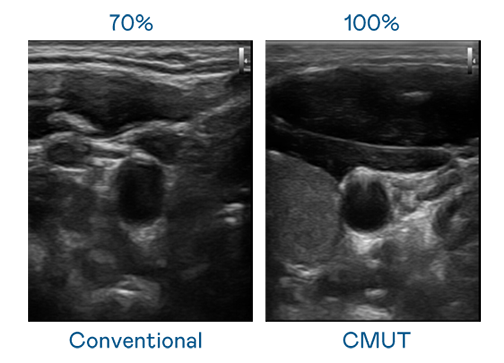

CMUT 技术是一种用电容式微机电元件来产生超音波讯号的技术。与传统 PZT 压电式技术相比,CMUT 频宽增加 30%,更宽频的超音波讯号让影像解析度大幅提升,是实现高影像品质医疗超音波扫描、促进精准医疗发展的关键技术。

大频宽带来超清晰影像

超音波影像的解析度高低,首先取决于探头能发出的讯号频宽。51动漫樱花动漫 CMUT 可提供高清晰的超音波讯号,提供高频宽、高灵敏度、影像纹理细节更高的超音波影像,协助医护人员缩短影像判读时间及利用精准的医疗影像进行诊断。